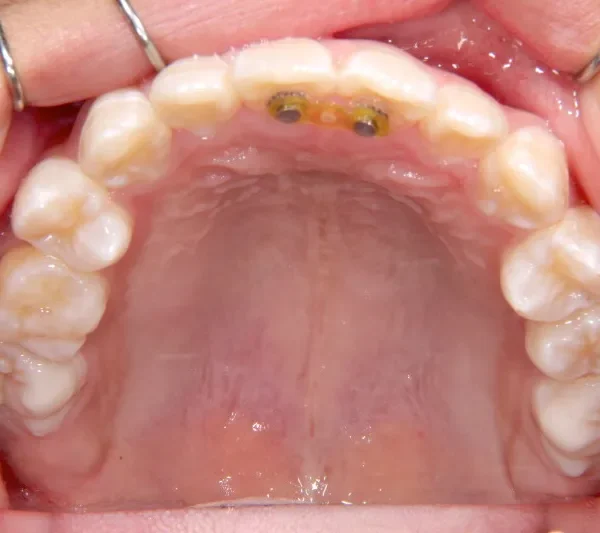

【子供の矯正(一期)】叢生・開咬・前歯で噛めない・舌癖・7歳女児【M.O様】

初診時年齢 小学校1年生 (女性) 主訴 前歯で噛めない

診断名 叢生・開咬 装置名

拡大床

舌の癖によって下の前歯が出て、上の前歯が短いです。

取り外し式の装置で上下の歯並びを拡げて、下の前歯を引っ込めます。

初診